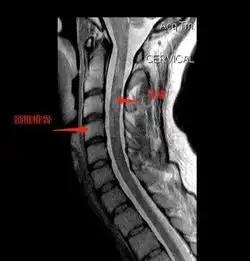

骨质增生图片

颈椎病图片